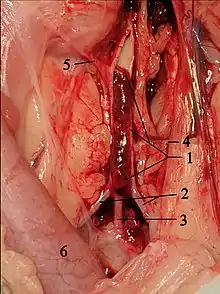

AO = Descending aorta; LV = Left ventricle; ECG = Electrocardiogram.

After the third QRS complex, the ventricle has more time to fill. Since there is more time to fill, the left ventricle will have more volume at the end of diastole (increased preload). Due to the Frank–Starling law of the heart, the contraction of the left ventricle (and pressure generated by the left ventricle) will be greater on the subsequent beat (beat #4 in this picture). Because of the dynamic nature of the outflow obstruction in HCM, the obstruction increases more than the left ventricular pressure increase. This causes a fall in the aortic pressure as the left ventricular pressure rises (seen as the yellow shaded area in the picture).

Upon cardiac catheterization, catheters can be placed in the left ventricle and the ascending aorta, to measure the pressure difference between these structures. In normal individuals, during ventricular systole, the pressure in the ascending aorta and the left ventricle will equalize, and the aortic valve is open. In individuals with aortic stenosis or with HCM with an outflow tract gradient, there will be a pressure gradient (difference) between the left ventricle and the aorta, with the left ventricular pressure higher than the aortic pressure. This gradient represents the degree of obstruction that has to be overcome in order to eject blood from the left ventricle.

The Brockenbrough–Braunwald–Morrow sign is observed in individuals with HCM with outflow tract gradient. This sign can be used to differentiate HCM from aortic stenosis. In individuals with aortic stenosis, after a premature ventricular contraction (PVC), the following ventricular contraction will be more forceful, and the pressure generated in the left ventricle will be higher. Because of the fixed obstruction that the stenotic aortic valve represents, the post-PVC ascending aortic pressure will increase as well. In individuals with HCM, however, the degree of obstruction will increase more than the force of contraction will increase in the post-PVC beat. The result of this is that the left ventricular pressure increases and the ascending aortic pressure decreases, with an increase in the LVOT gradient.

While the Brockenbrough–Braunwald–Morrow sign is most dramatically demonstrated using simultaneous intra-cardiac and intra-aortic catheters, it can be seen on routine physical examination as a decrease in the pulse pressure in the post-PVC beat in individuals with HCM.